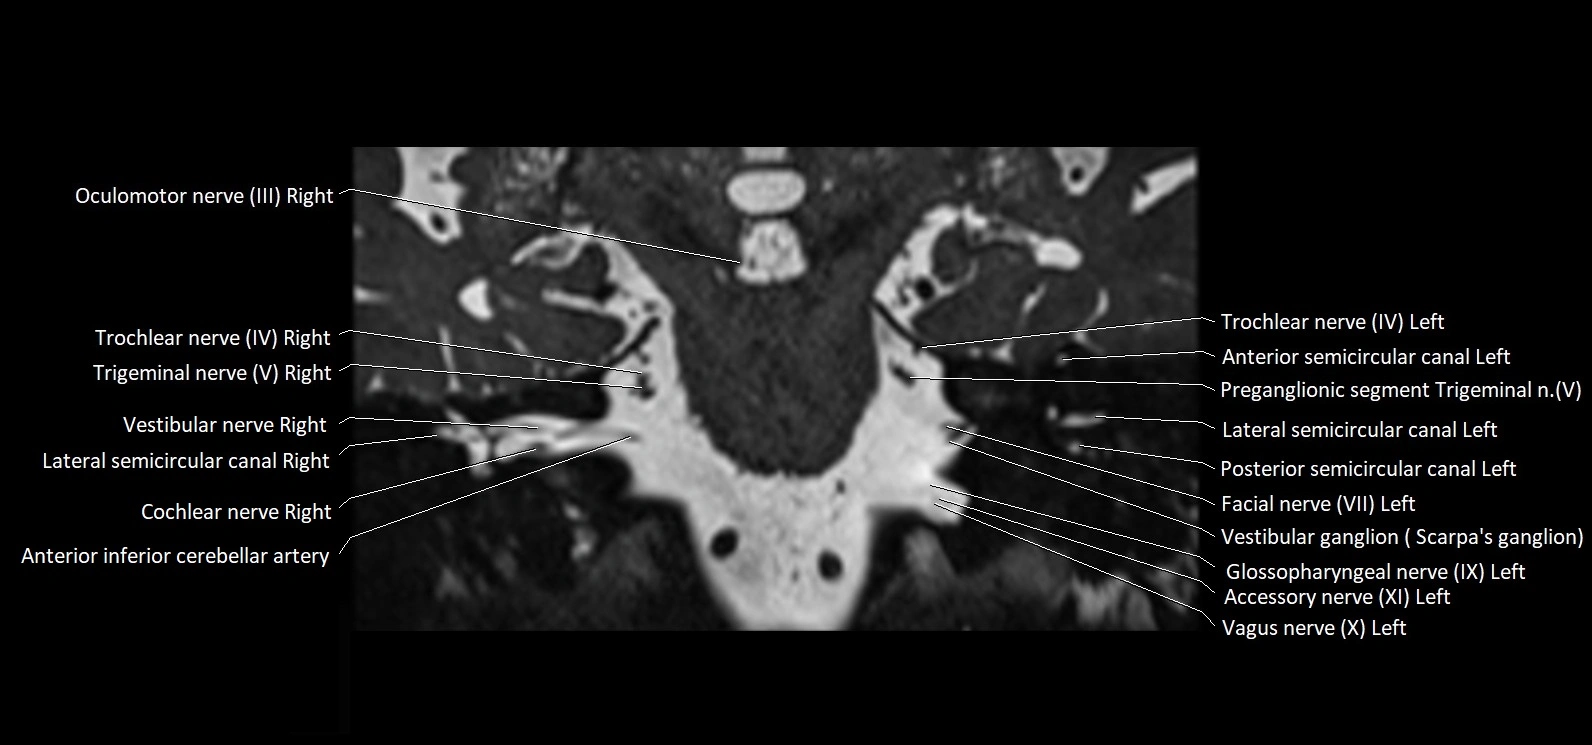

MRI Appearance

• The abducens nerve is a small, thin, linear structure

• Best visualized on high-resolution T2-weighted 3D MRI sequences (e.g., FIESTA or CISS)

• Seen as a hypointense (dark) line running from the brainstem at the pontomedullary junction, traversing the prepontine cistern, and entering Dorello’s canal under the petrosphenoidal ligament, then into the cavernous sinus, and finally the orbit

• May be challenging to visualize in standard MRI due to its small size

• Pathology may be inferred by absence, displacement, or enhancement of the nerve

MRI images

image